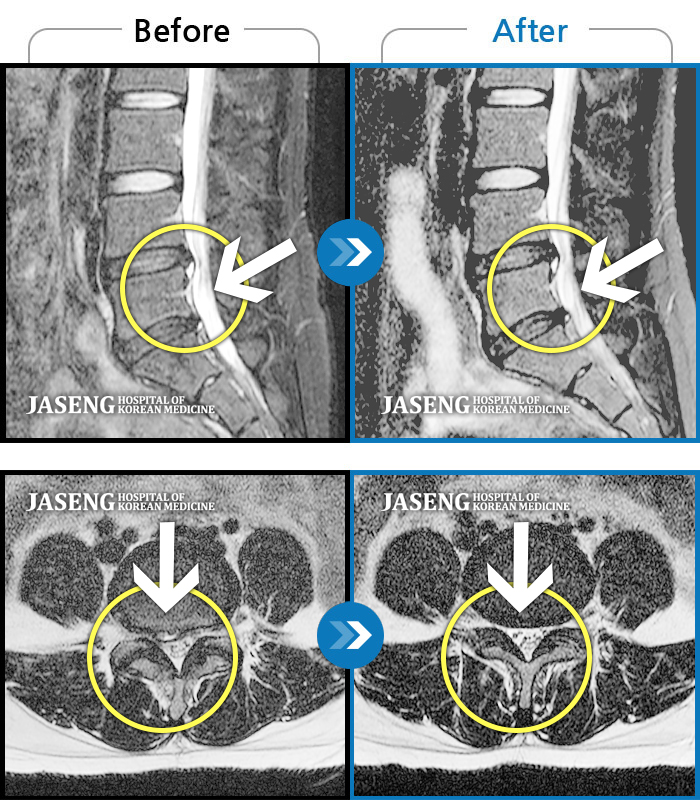

허리디스크

인천 · 강아현 원장

우측 허리 통증 및 다리 저림이 심하여 앉거나 바로 눕는 것도 힘든 상태로 내원하셨습니다. 감각 저하도 동반되어 심각한 신경손상이 의심되는 상황이었습니다.

촬영시기

2024.07.27 ~ 2025.04.05

2025.04.16